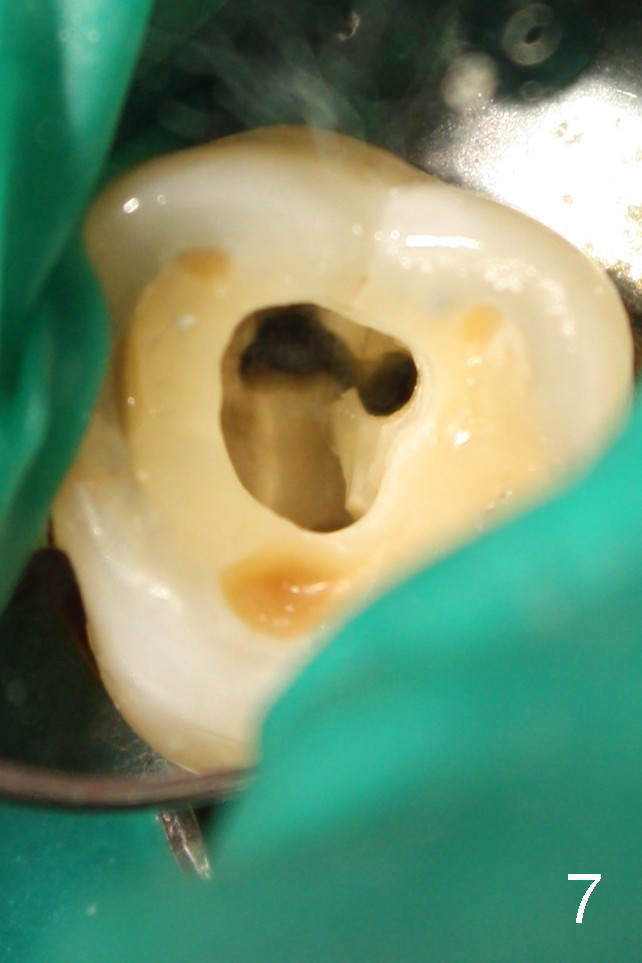

50岁男士有严重牙周炎(图一(2009年拍摄):二号牙(左上七)最终拔除(与图二对比)),最近三号牙(左上六)冷热痛,而且不能咬东西,三号牙多处牙周袋深,根尖片显示远中颊侧和腭侧根尖阴影(图二箭头),初步诊断:牙周牙髓综合症,需要根管治疗以及牙周手术,还可能保留不了。开髓表明活髓,近中颊侧和远中颊侧(DB)根管口很接近(参考图一图二),扩大(30/.04)后并表现不出来(图五至图七),开始近中根管口好像比较接近腭侧根管口,以为是MB2,使用Piezo超声波/diamond tip在MB(图六*)颊侧和近中寻找另外一个根管(箭头),但不成功。腭侧根管扩大到40/.06,匆匆忙忙插入主牙胶尖,拍摄根尖片(图三),显示远中颊侧以及腭侧(P)牙胶尖在相应牙根正中,但是近中颊侧并不是这样(图四=图三+MB牙根和牙胶尖轮廓),这说明还存在另外一个根管。经过再次合适扩大(crown down),腭侧牙胶尖进入更深地方(临床上),这时病人已经坐立不安了,paper points吸干根管后,拍摄图五至图七,暂封。由于病人还缺失好几颗牙齿,劝他去拍摄CT。今天术后第五六天,打电话给他,他很高兴,说冷热痛消失,牙齿也牢靠多了,但是还没去拍摄CT。下周三他回来完成根管治疗。

如果他还没有CT,我该怎么在没有外科显微镜下找遗留根管呢?MB和P根管口之间的确有一个沟(map),但是非常光滑(图五至图七),能找到根管口?还是往原来MB根管口颊侧探索?图三/图四暗示MB1还没有被发掘,对吗?MB2存在吗?